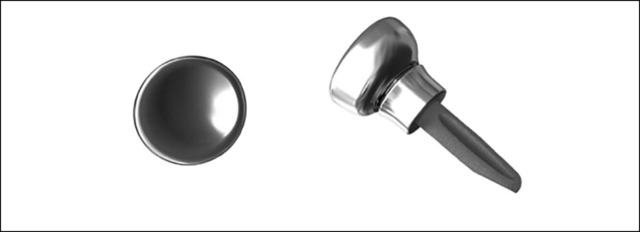

松配型(loose-fitting)假体

根据假体与桡骨骨质的关系,有些桡骨头关节假体被归为松配型(见图 5)。根据桡骨头、桡骨颈、桡骨干的大小设计相应的桡骨头假体。假体柄被设计成可以安放在原始桡骨头的解剖位置,形成稳定肘关节的构件。理论上讲,和可能被放置于非解剖位置的压配型假体相比,类型的假体不会出现松动和内置入物疼痛。当肘关节活动时,松配型型假体可以“回缩”(dial in),在运动过程中肱骨小头更好的完成匹配。松配型假体的理论优势在于可以适应桡骨头假体与自身桡骨头的差别。但是,该类型假体仍有可能存在肱桡关节过度填塞的问题。

图 5 A Evolve 松配型假体具有组装式的桡骨头和光滑的柄。前后位(B)和侧位(C)X 线显示使用 Evolve 型假体治疗的一例 Mason-Johnston 分型 III 型桡骨头骨折

最近的临床证据显示松配型假体可以取得良好中短期疗效。Chien 等人使用松配型型假体治疗 10 例桡骨头骨折和 3 例桡骨头骨不连患者,平均随访 38 个月(范围 20 至 70 个月)。Mayo 肘关节表现评分获得明显改善,8 例患者疗效为优,3 例良,2 例可。没有 1 例患者因为假体松动而去除桡骨头假体,也未发现肱骨小头出现磨损。

Doornberg 等人使用松配型型假体治疗合并肘关节不稳的桡骨头骨折同样取得了良好疗效。27 例患者中有 17例出现桡骨颈部位的 X 线透亮带,9 例患者出现肱骨小头磨损,但是上述患者均未报告存在有与上述情况有关的疼痛。

考虑到这一类型的假体是被人为设计有意松散放置的,因此桡骨颈假体柄周围的透亮带是无法避免的,而这些透亮带的临床影响微乎其微。没有研究数据评估该类型假体的透亮带达到何种程度就会对临床疗效造成影响。根据现有证据,虽然目前还很难判断松配型型假体是否优于压配型假体,但是该类型假体确实可以起到缓解疼痛、重建肘关节的稳定性的作用。